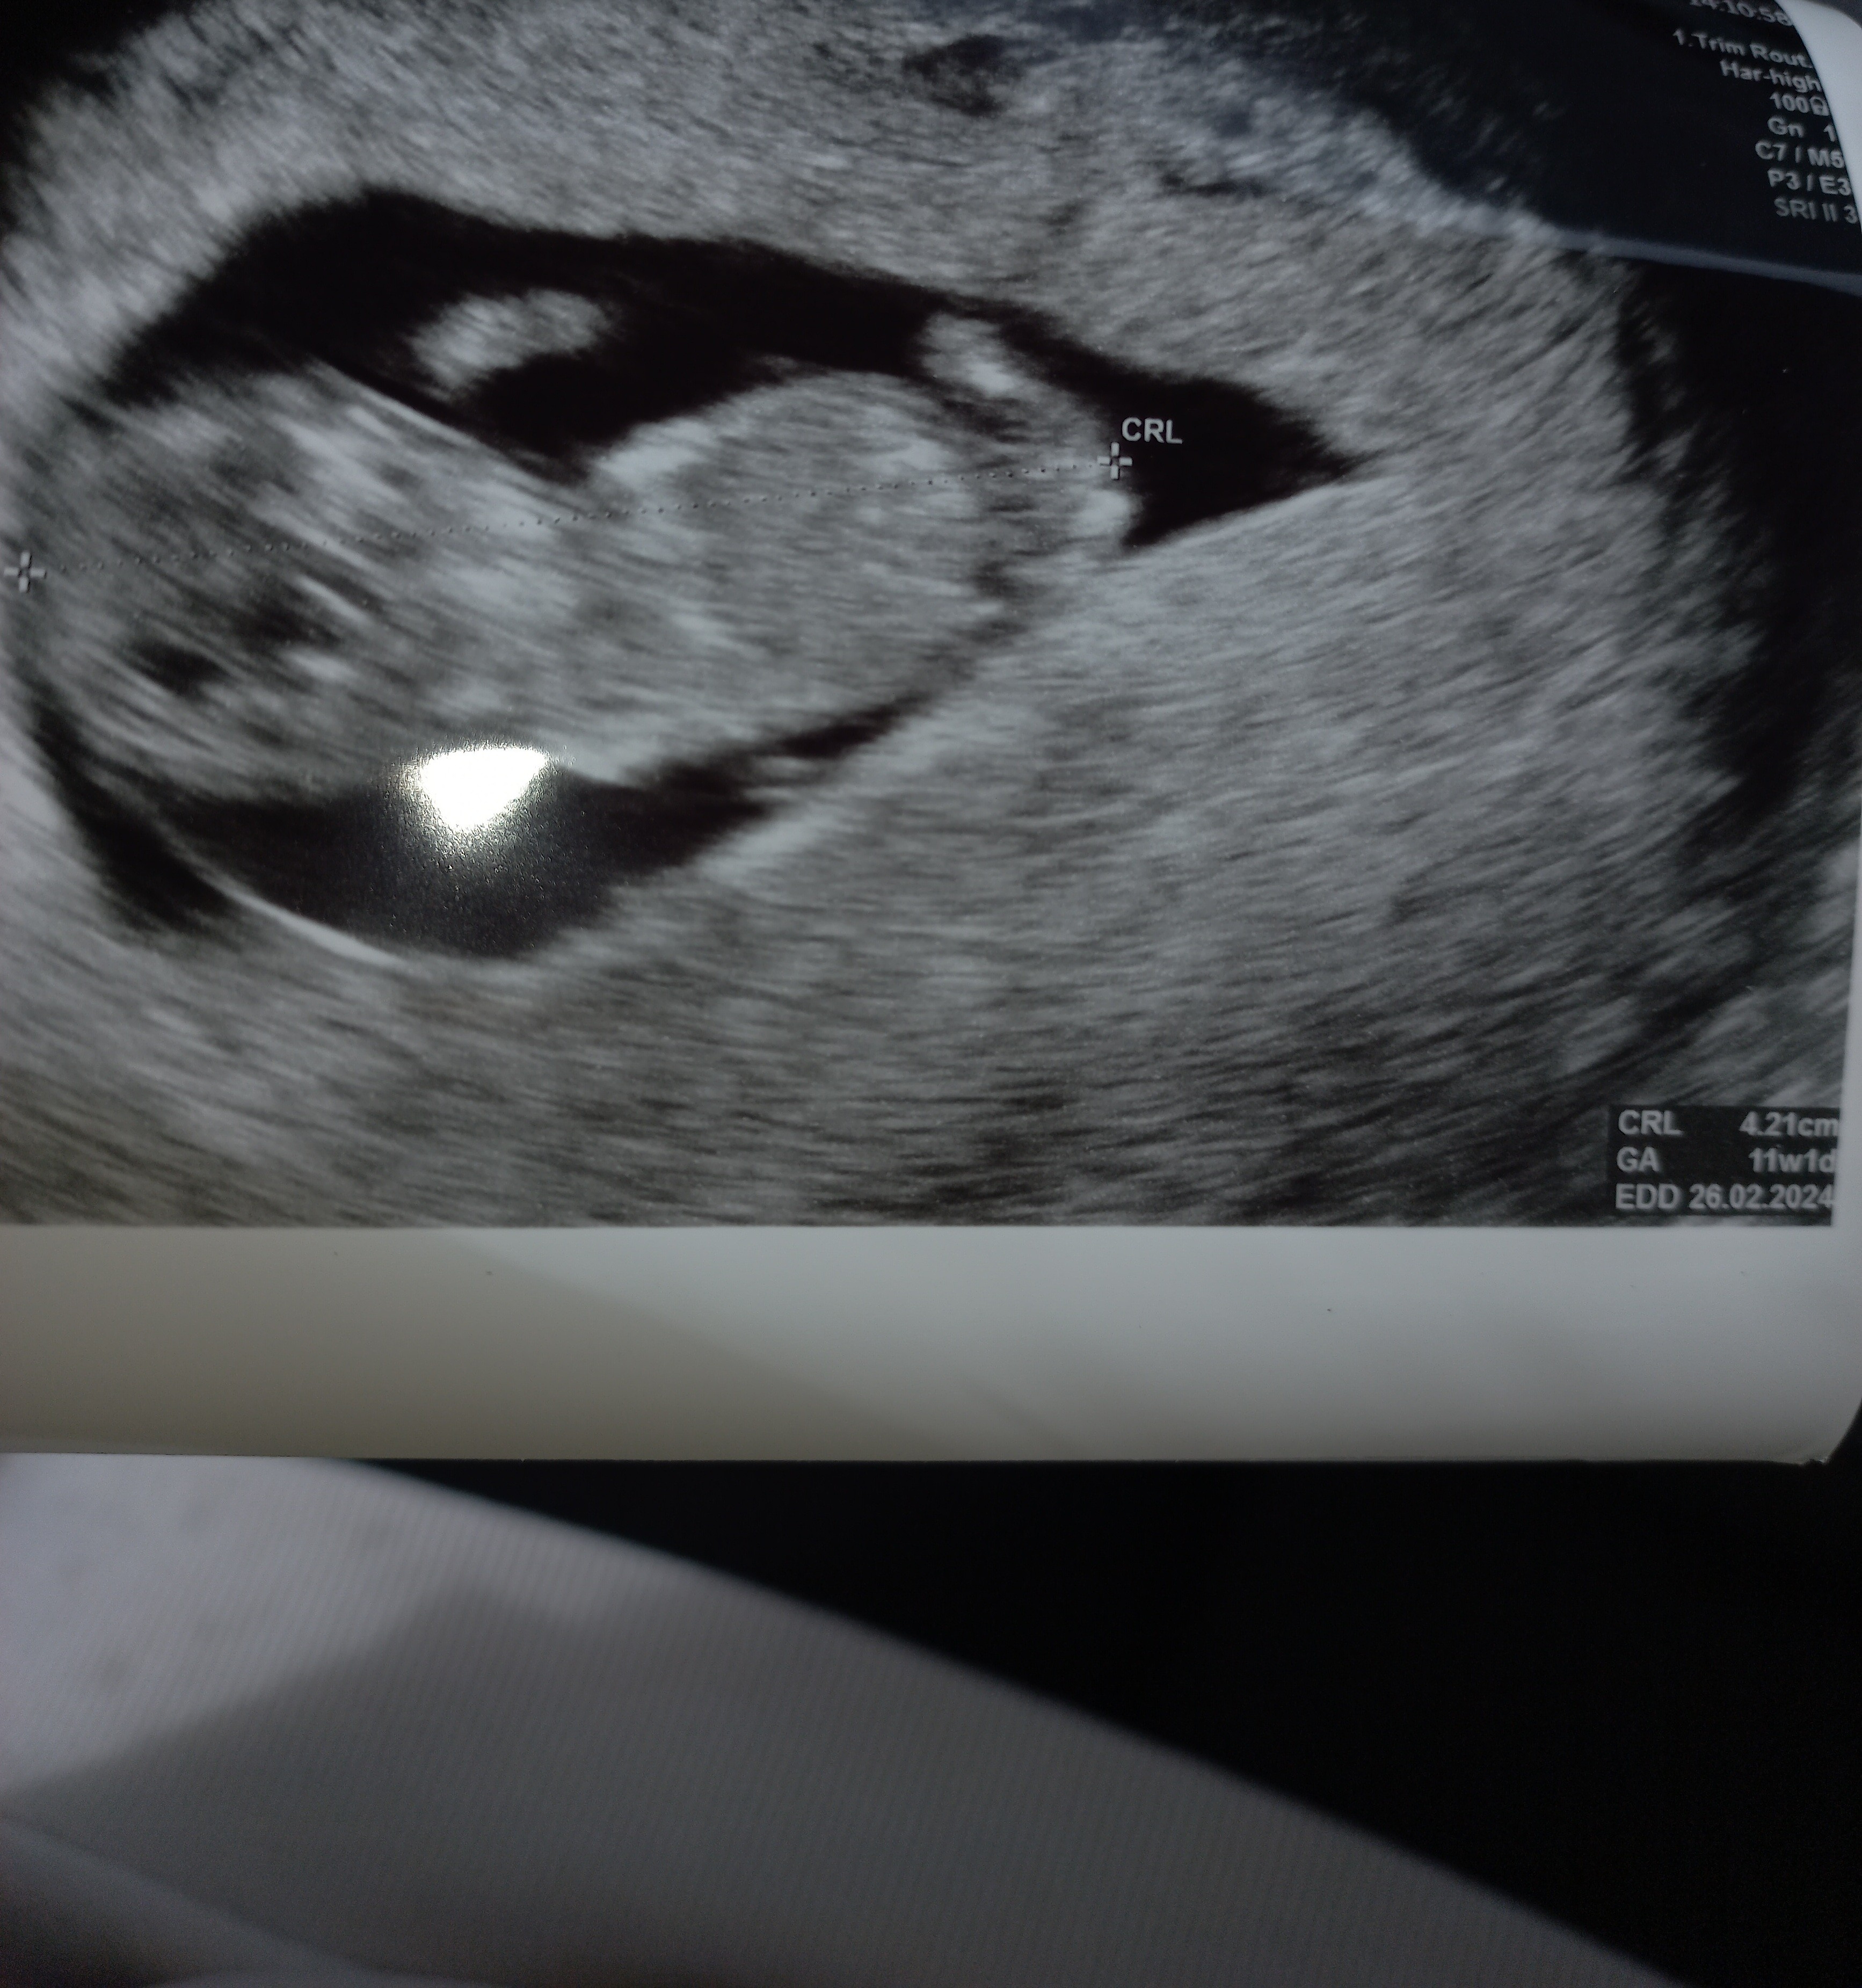

Moja dzidzia wszystko ok serduszko 173 uderzeń być morze dziewczynka 🙂